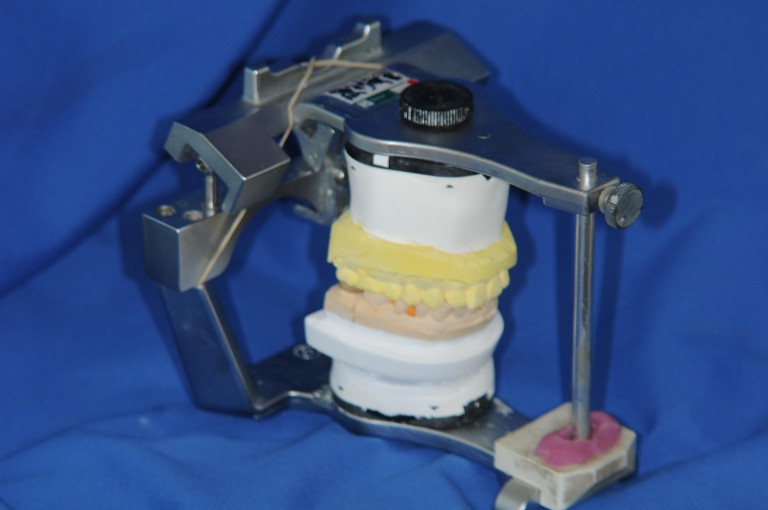

取面弓,上咬合器